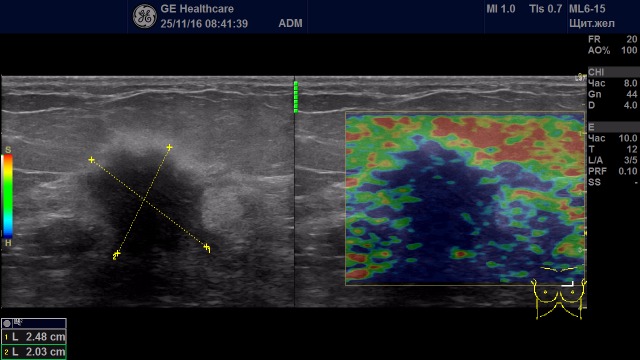

Образование с удовлетворительной эластичностью